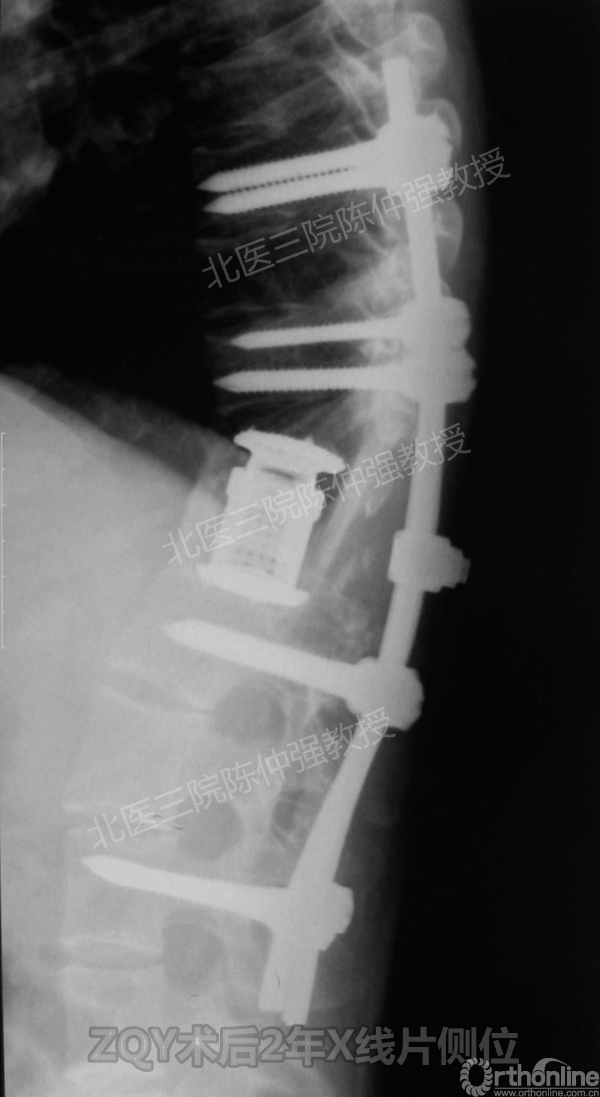

2005年,陈仲强教授在AOSpine年会上分享了一例胸腰椎陈旧结核性侧后凸畸形病例。资料如下:

ZQY术后2年

患者女性17岁,胸腰椎陈旧结核性侧后凸畸形,局部呈“麻花状”扭转,无神经功能受损表现。2005年,陈仲强教授带领团队实施后路+侧前方联合入路脊柱节段切除、双轴旋转矫形术。术后患者外观显著改善,神经功能正常。术后随访证实患者截骨矫形节段骨性融合良好,矫形效果持续良好。